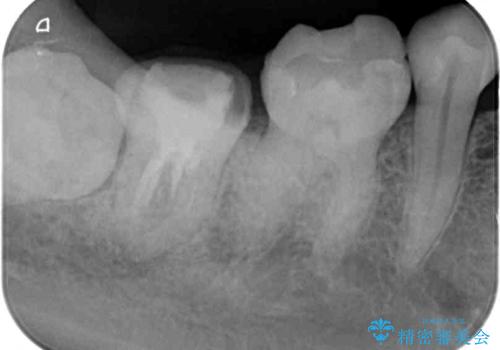

- かかりつけ医にて、歯の高さが不足しているためセラミッククラウンの装着はできないと言われたとのことで来院された患者様です。

診察したところ、確かに歯の高さは不足していましたが、土台の立て直しや歯の削り方を調整することでオールセラミッククラウンでも補綴可能と思われました。

ただし、クラウンの厚みは極力薄くした方が維持力が増すため、高強度のフルジルコニアクラウンにて補綴治療することとしました。